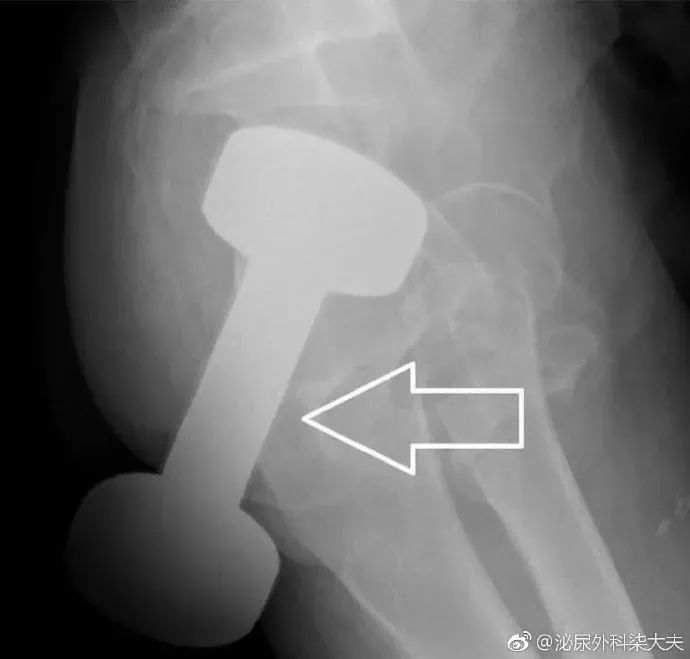

一位50多岁的男子发现了这种新奇玩法,把重达10斤的哑铃塞进了肛门。

医生会通过一系列检查如直肠指诊、X线来确定体内的异物是什么,在什么位置,这一点非常关键,因为只有搞清楚里面的真实情况,医生才能找到合适的方法把异物取出。 一些小的、圆的异物,像小跳蛋、玻璃球,一般可以自行排出。 如果不行的话就需要在腰麻等麻醉下充分扩肛后取出,对于果壳、鱼刺与粪便结成的大团块,可灌入石蜡油后用卵圆钳夹碎,分块取出。